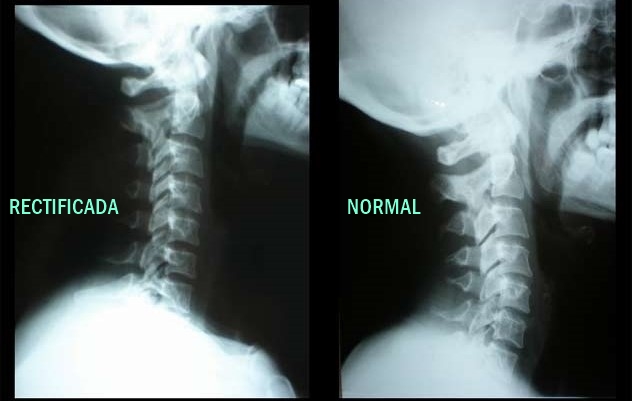

Corrección postural

Alinea tu Columna

Corrección de columna, ajustes vertebrales y valoración postural para aliviar dolor de espalda, cuello y articulaciones.